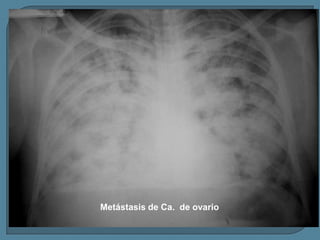

Metástasis de Ca. de ovario